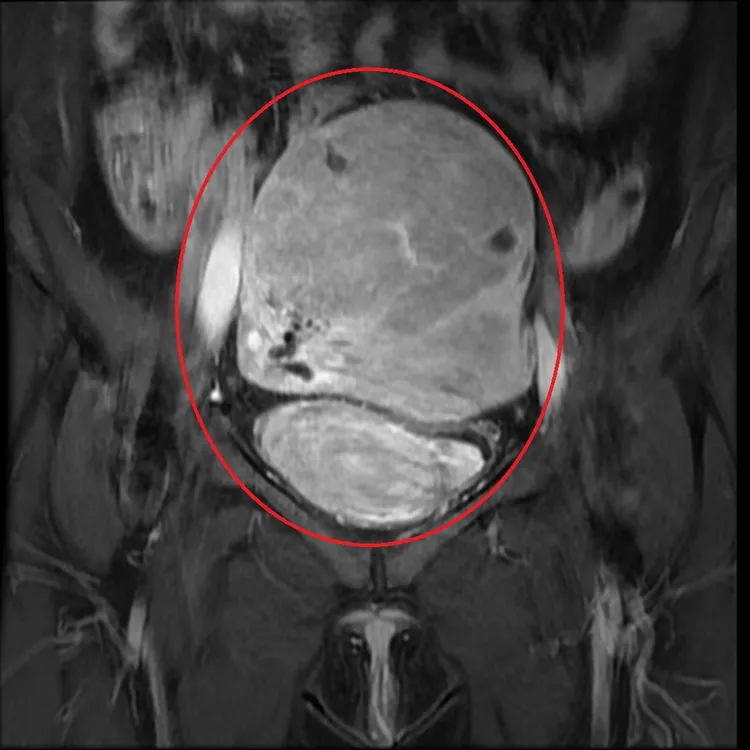

子宮肌腺症病灶檢查影像圖片。亞大附醫提供

高惠芬指出,「子宮肌腺症」是指子宮內膜細胞浸潤到子宮肌肉層形成急性及慢性發炎反應,發生率約在20-35%,往往會讓女性朋友出現經痛症、月經量多或慢性骨盆疼痛等等症狀,醫師會依每位患者的個別性,選擇藥物或手術治療,手術治療也可以選擇切除部份子宮肌腺症病兆(建議術後賀爾蒙治療減少日後復發的機會)或是根除性子宮切除手術治療。